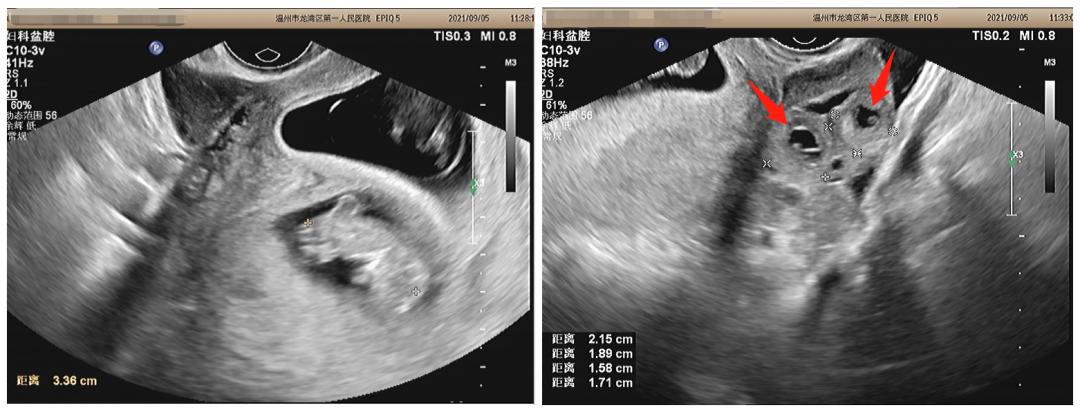

经过B超检查发现,龚女士的 子宫内有两个胚胎,子宫外输卵管的部位,还有两个胚胎。

龚女士B超检查单——

红色箭头处便是跑到宫外的“两个淘气宝宝”